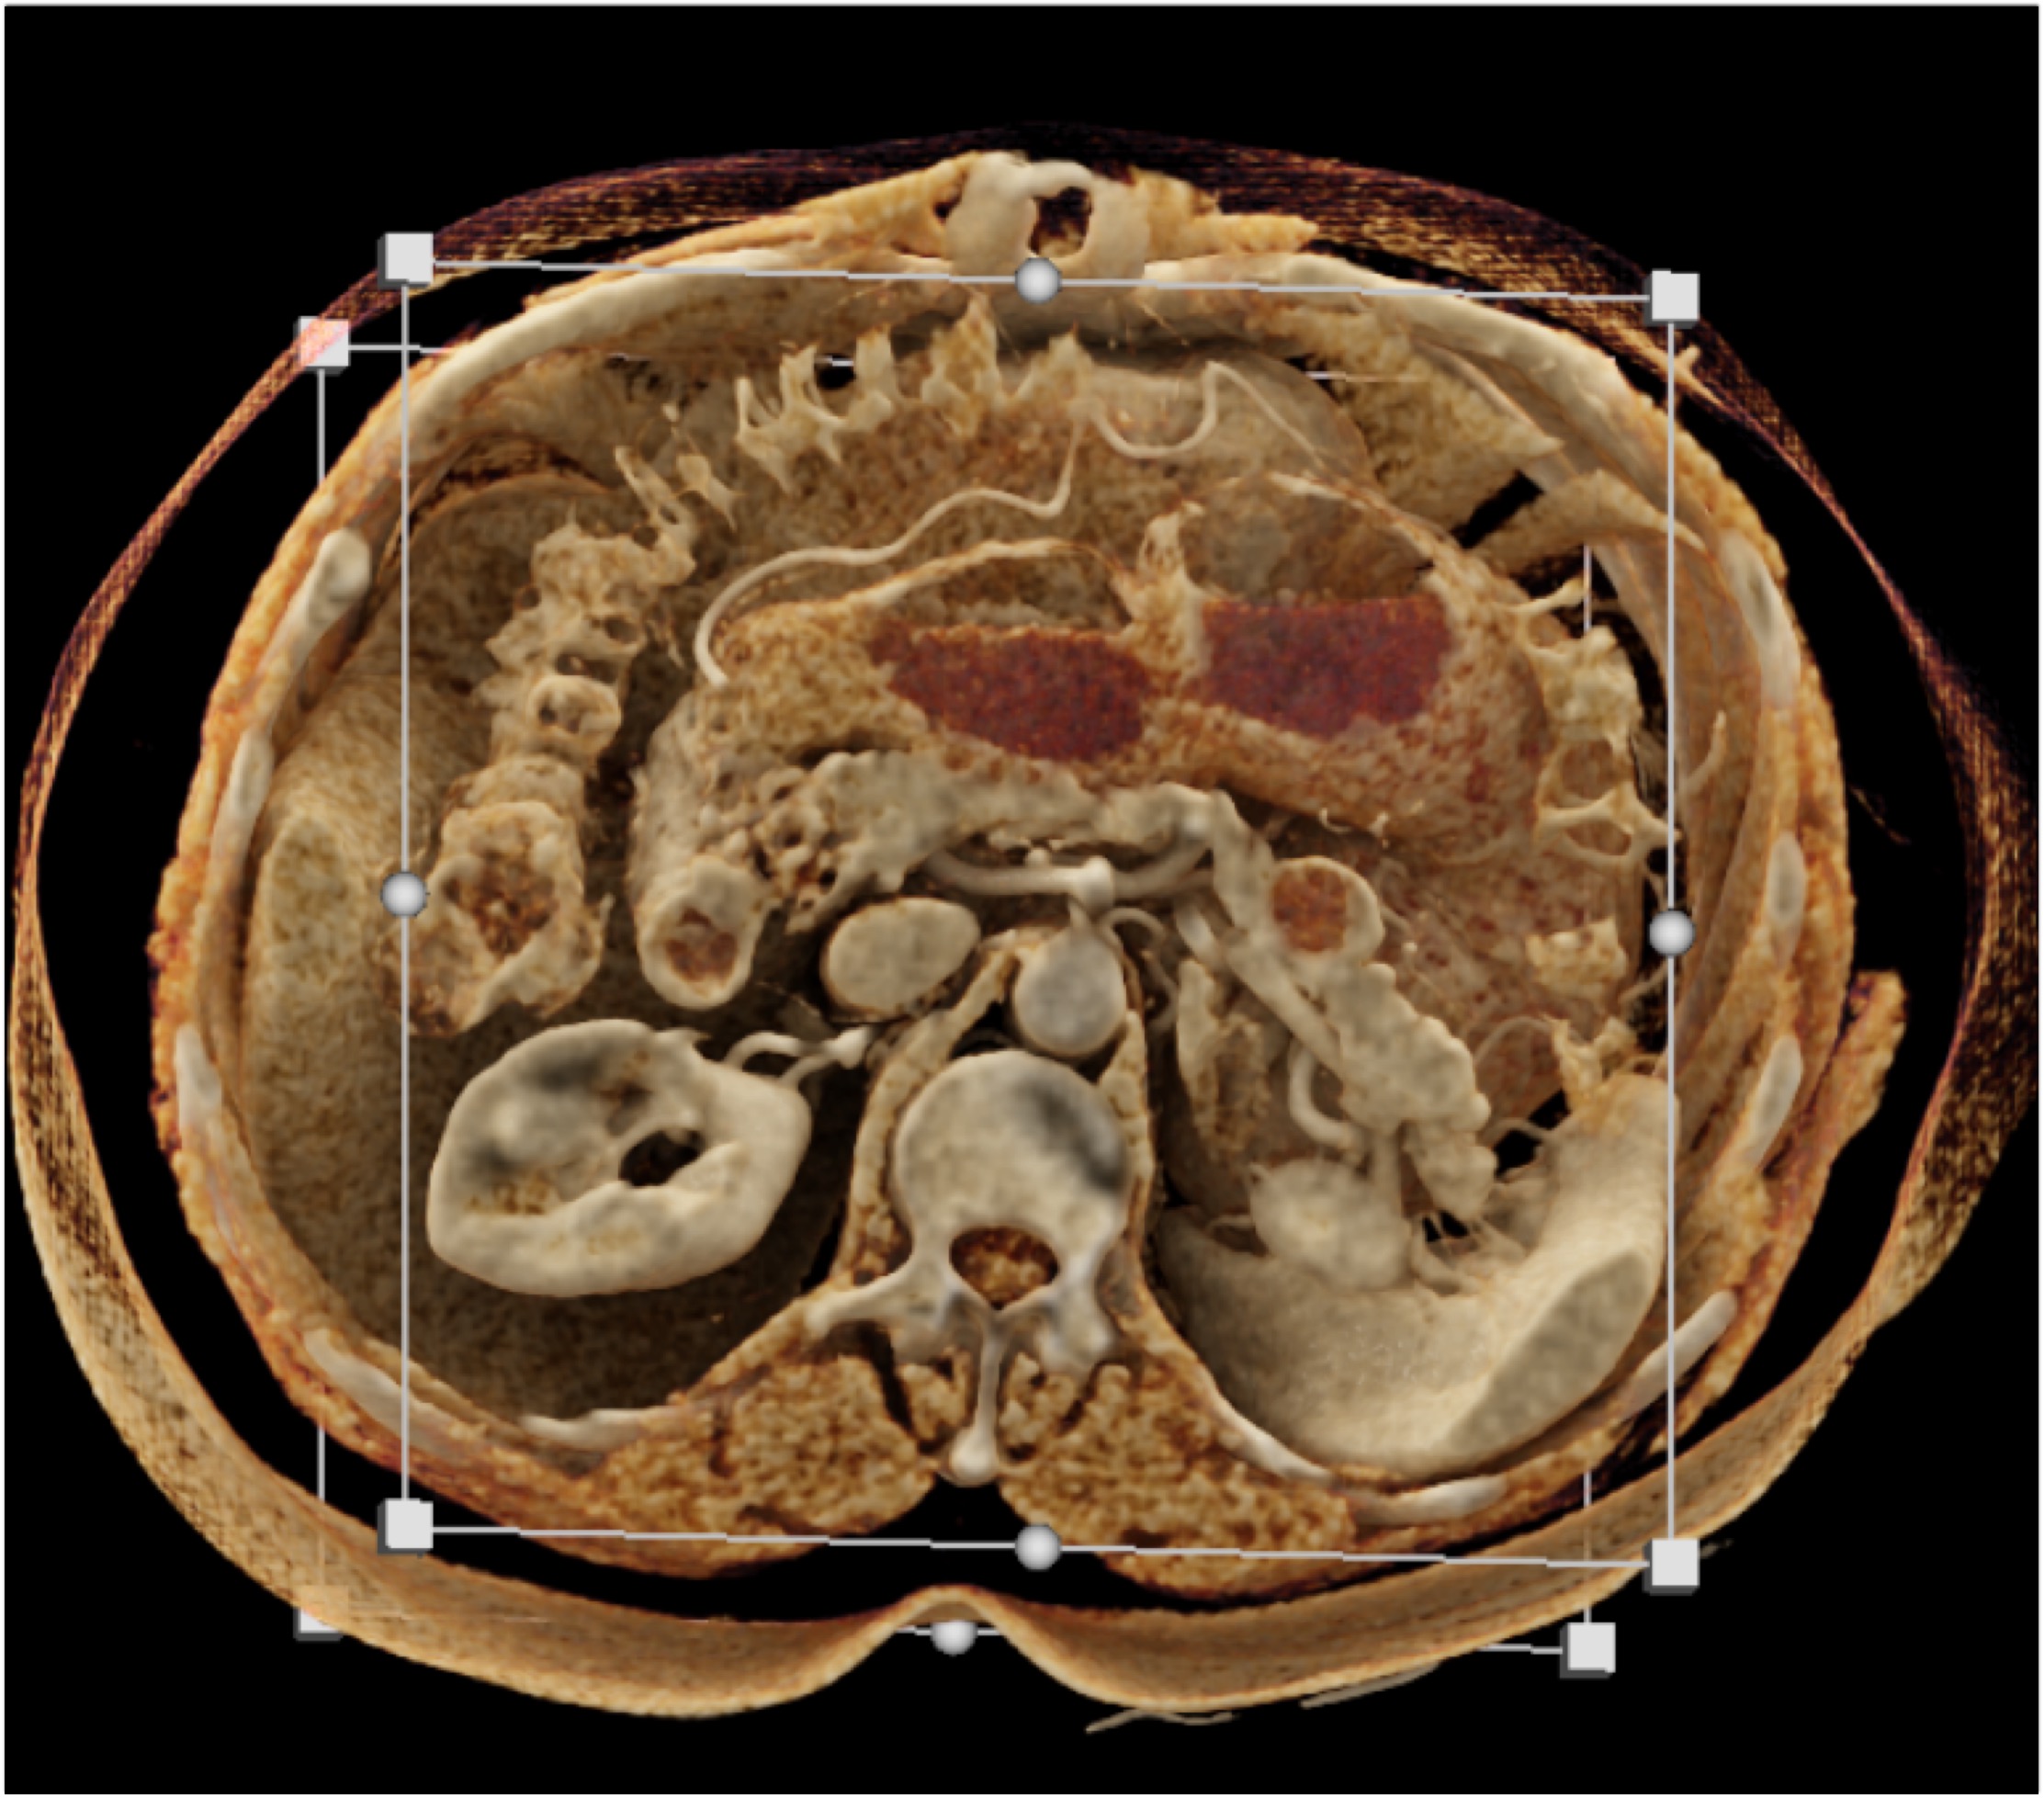

6) The most likely diagnosis in this case is?

lymphoma

acute pyelonephritis

XGP (xanthogranulomatous pyelonephritis)

TB